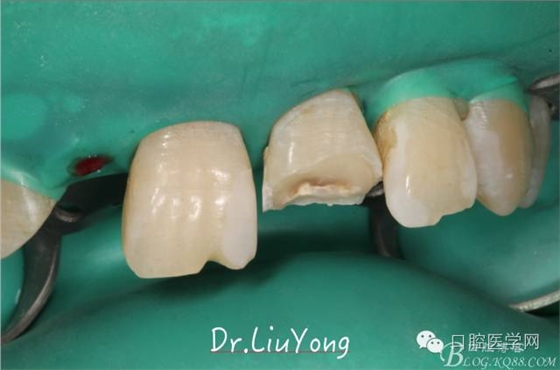

由于上前牙外傷后未及時行松牙固定,已拖延1月,因此先行松牙固定,嘗試保留。因A2冠根折,牙冠缺失,故行A1-B3松牙固定,選擇鄰面樹脂粘結(jié)固定,因?yàn)檠例l極易出血,因此選擇橡皮障下用流體樹脂進(jìn)行松牙固定。同時A2B1根管治療。